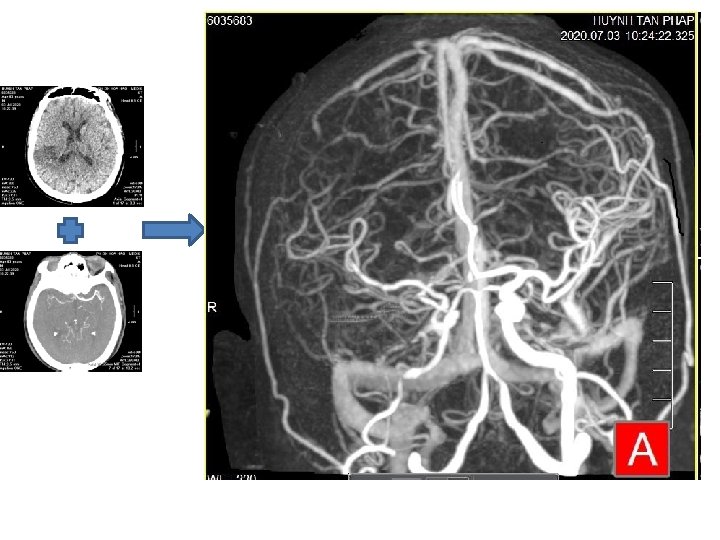

SUBTRACTION CTA • In subtraction CT angiography (s. CTA), a noncontrast CT acquisition is subtracted from a contrast-enhanced CTA acquisition.

SUBTRACTION CTA • Subtraction is a post-processing technique to eliminate high-density structures, such as bone, metal, calcification, from CT images. • A subtraction dataset is obtained by subtracting a non-contrast acquisition (mask image) from a contrast-enhanced image.

DEDICATED REGISTRATION ALGORITHM • This deformable registration algorithm matches the position of bony structures and calcifications on the mask image to the contrast scan prior to subtraction. • Accordingly, subtracted image data are obtained from which high-density structures have been removed and which can be used for evaluation in conjunction with the conventional contrast-enhanced images.

APPLICATION • Automatically remove bone, calcium and stents • Visualization of the true vessel lumen for better quantification • Whole body CTA, brain CTA, carotids, aorta, run-off • Zero-click workflow

A NUMBER OF CLINICAL APPLICATIONS FOR NEUROLOGICAL CT ANGIOGRAPHY • Cerebral aneurysms — especially close to the bone • Patients with ischemic disease — ICA, basilar artery • Cases with stenosis or occlusion — close to bone • Patients with a clip or coil • Patients with calcification • Patients with hypervascular tumor • Patients scanned from neck to head